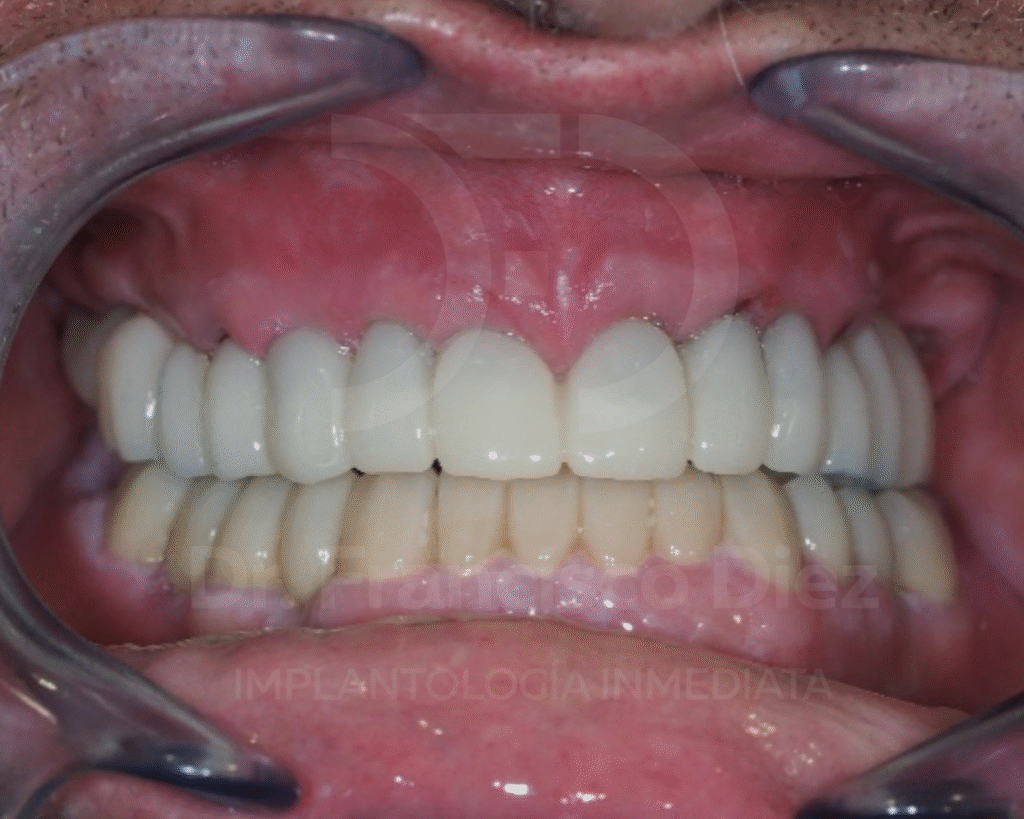

El mismo días de la intervención se colocó una prótesis fija provisional fabricada en PMMA, permitiendo al paciente recuperar la función masticatoria y la estética de forma inmediata.

Esta prótesis se utilizó durante 8 meses, periodo necesario para la remodelación ósea y la estabilización de los tejidos, y se remplazó por una prótesis de circonio con estructura de titanio.

El paciente experimentó una mejora inmediata en la masticación, el aspecto estético y la calidad de vida, con una recuperación rápida y sin complicaciones.